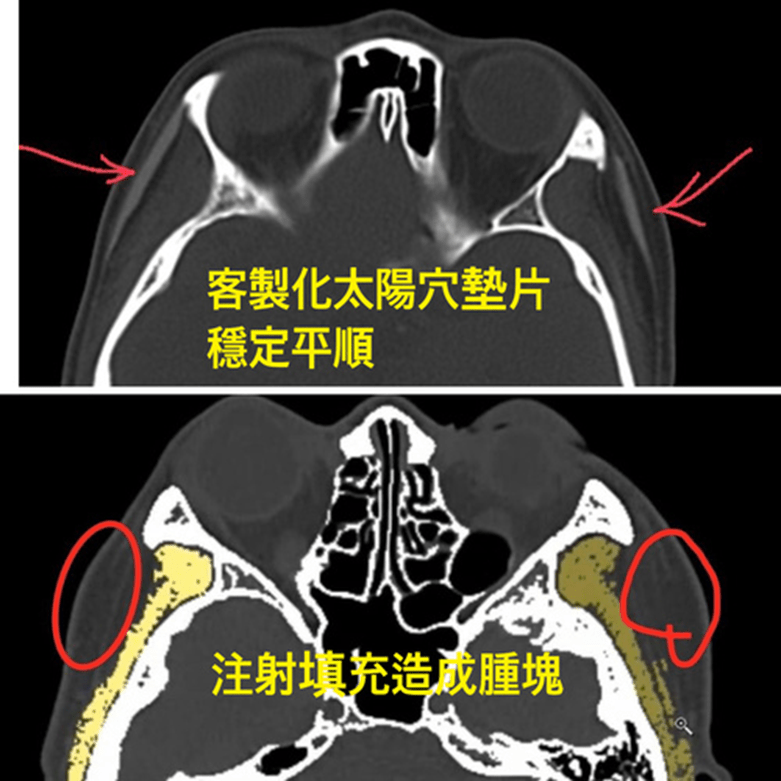

1. 注射填充——如玻尿酸或其他人工填充劑,但因為咀嚼肌的活動,這些材料會比其他部位更快吸水膨脹和變形及移位,容易造成不平整。可能出現凹凸、吸收、移位往往需要一再修補觸逐漸的饅化與走形。下圖3D電腦斷層掃描可見填充劑在組織纖維間隙的堆疊。凹凸不平是合理的,修補容易逐漸饅化。

下圖: 3D電腦斷層掃描下發現填充注射後的材料不平均的堆疊

電腦斷層發現:下圖為墊片位置穩定平順(紅色箭頭),下下圖紅圈處為注射脂肪下移與吸收不均的腫塊。為李醫師客製化墊片手術後兩年半長期和太陽穴注射填充結果比較:

Filler/ fat augmentation is quite different from the implant sheet on temple area. Long term results show on 3D CT scan, we can find the filled temple disfigured a lot compared with the implant sheet on temple contour.

範例 二:淺藍色為墊片(黃色為肌肉部分)

上圖:在3D電腦斷層掃描顯像:微創墊片在太陽穴(近三年)和注射填充的效果對比